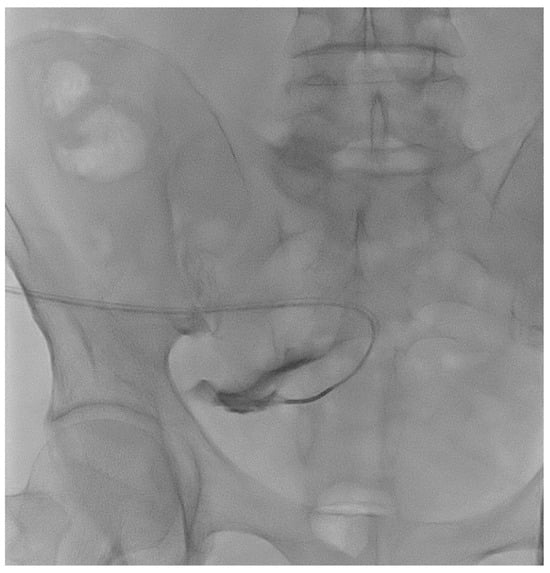

A 77-year-old male patient with ESKD secondary to diabetic kidney disease underwent placement of a “Vicenza Short”peritoneal catheter by open surgical dissection under local anesthesia. Peritoneal dialysis was started after two weeks, but poor drainage performance with a large residual volume was immediately observed. An abdominal X-ray documented coprostasis and the right location of the peritoneal catheter tip in the pelvis. The patient tried different laxatives and enemas without improvement in the outflow performance of the catheter. The patient underwent catheterography that demonstrated regular inflow but impeded outflow function. The catheter appeared to be stuck on the postero-lateral side of the iliac right region (Figure 2), and wire-guided manipulations failed to move it from its original position. The patient reported mild pain after the procedure that was easily relieved with oral acetaminophen.

Figure 2. Catheterography showing the peritoneal catheter with the tip (Life 14 01475 i002) ending in the right iliac region.